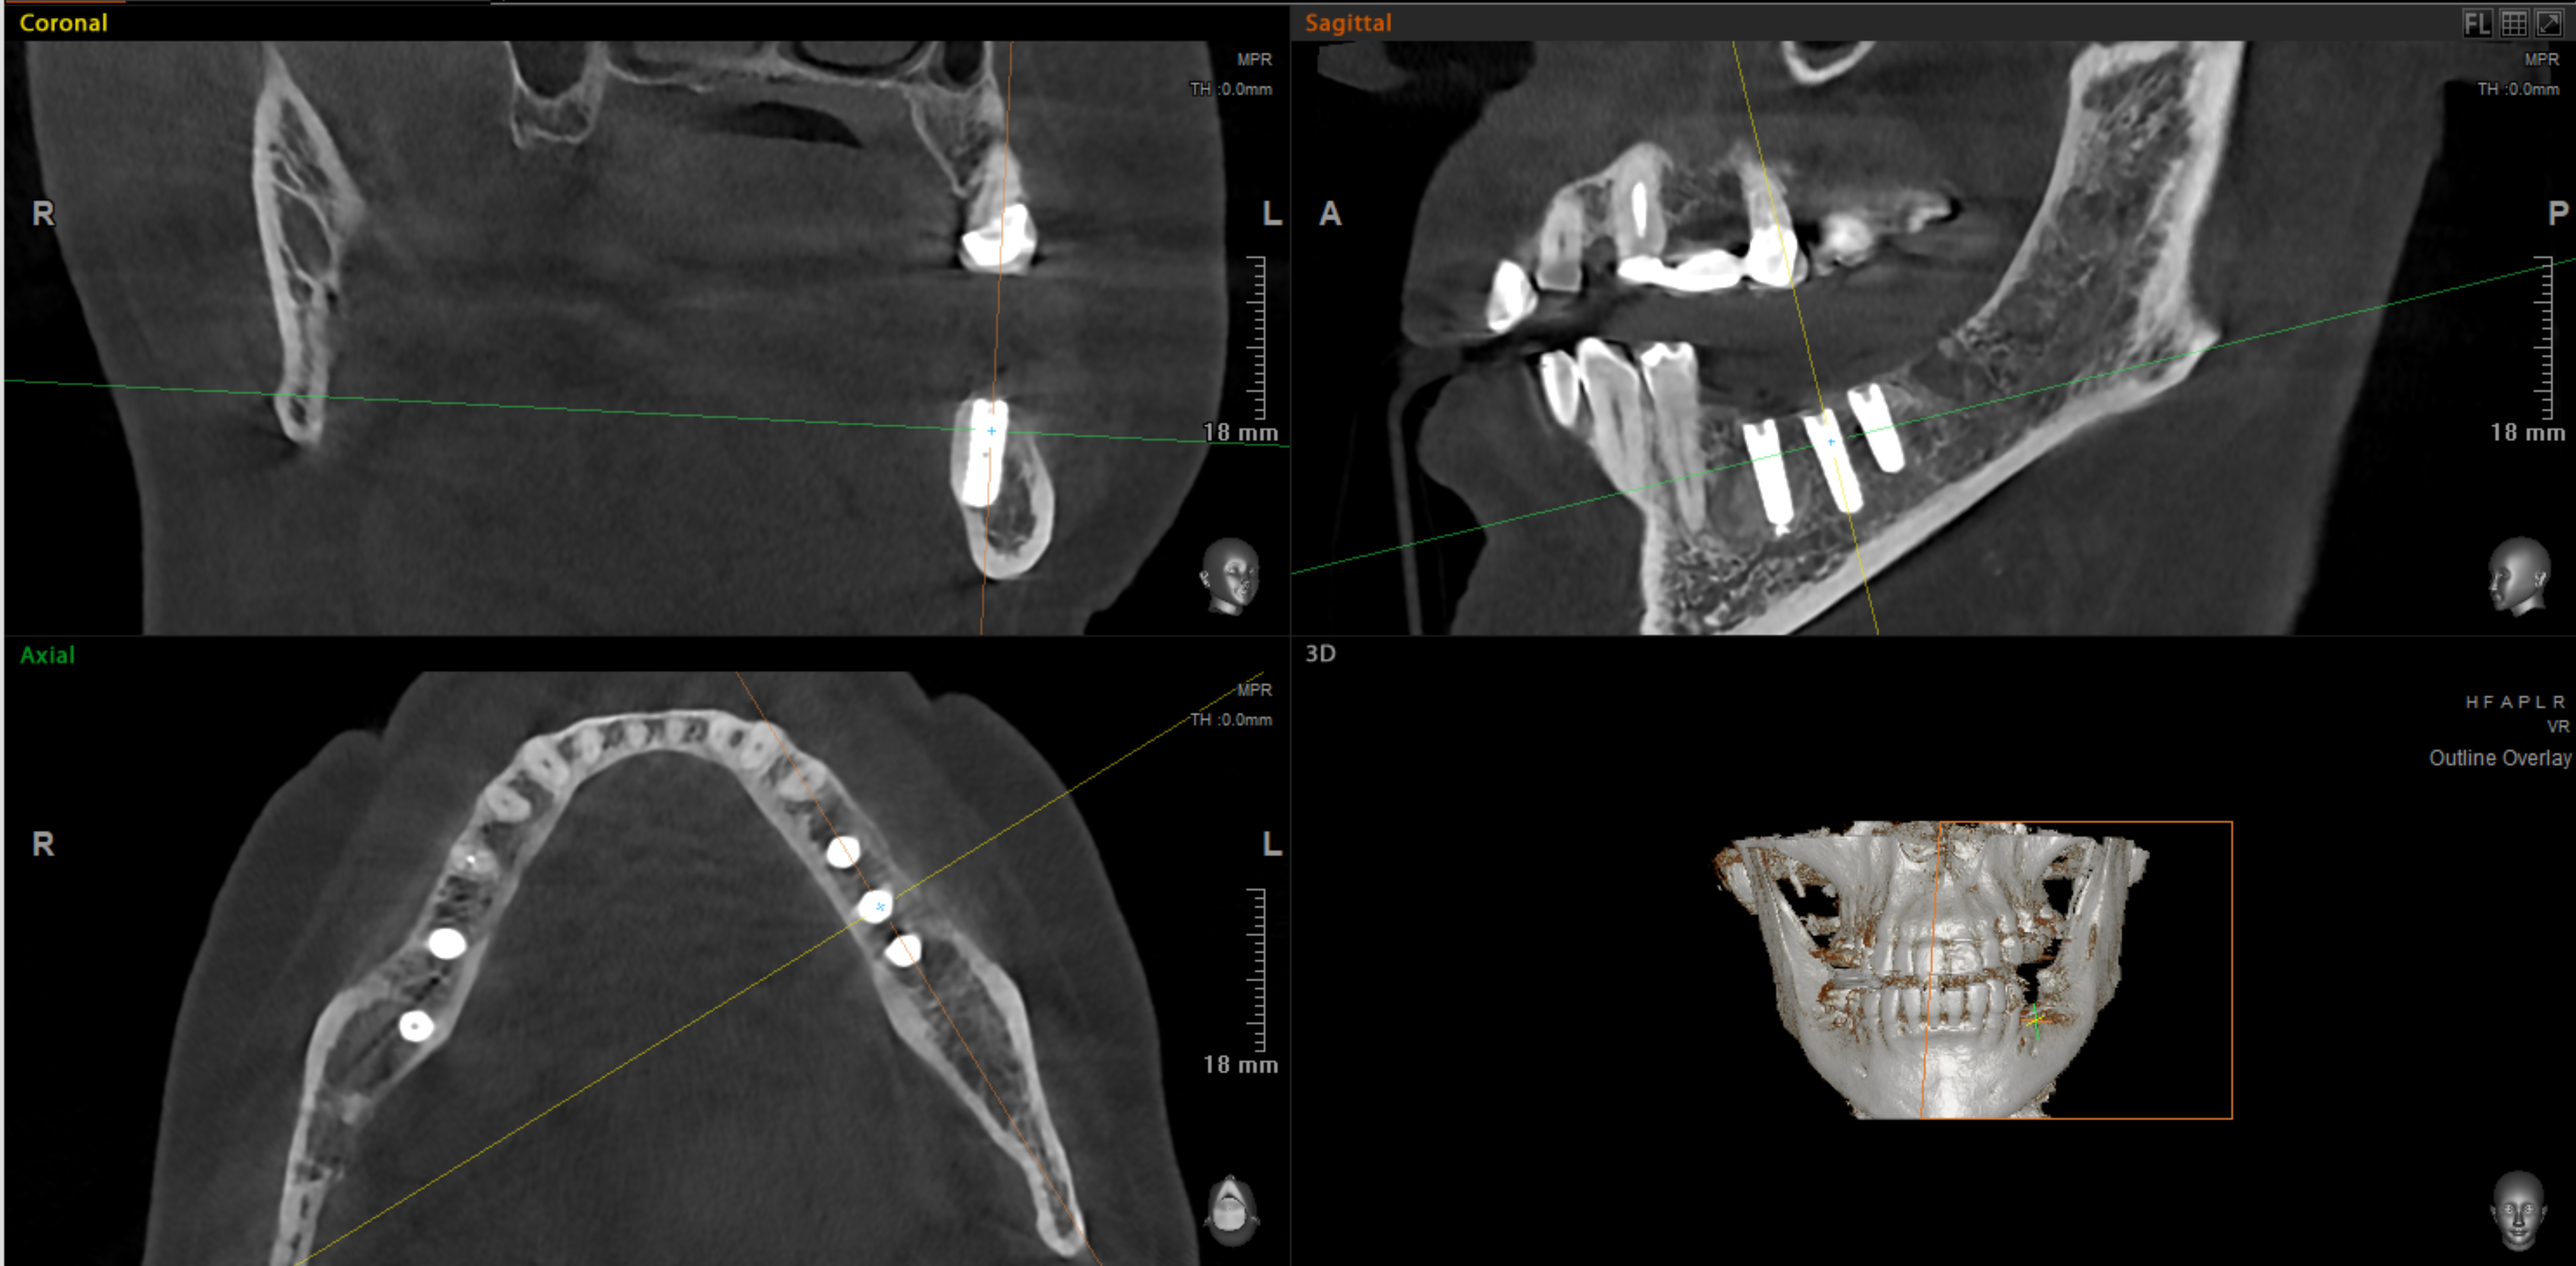

КЛинический случай ильи коробкова

отсроченная ИМПЛАНТАЦИЯ после удаления кисты

Пациентка 65+. Радикулярная киста в области зуба 35.

Удаление зуба с заполнением остаточной полости костным графтом.

Через 6 месяцев установка имплантов VEGA 3,5х12мм.- 2 шт. и 3,5х10мм.

Протезирование через 4 месяца.